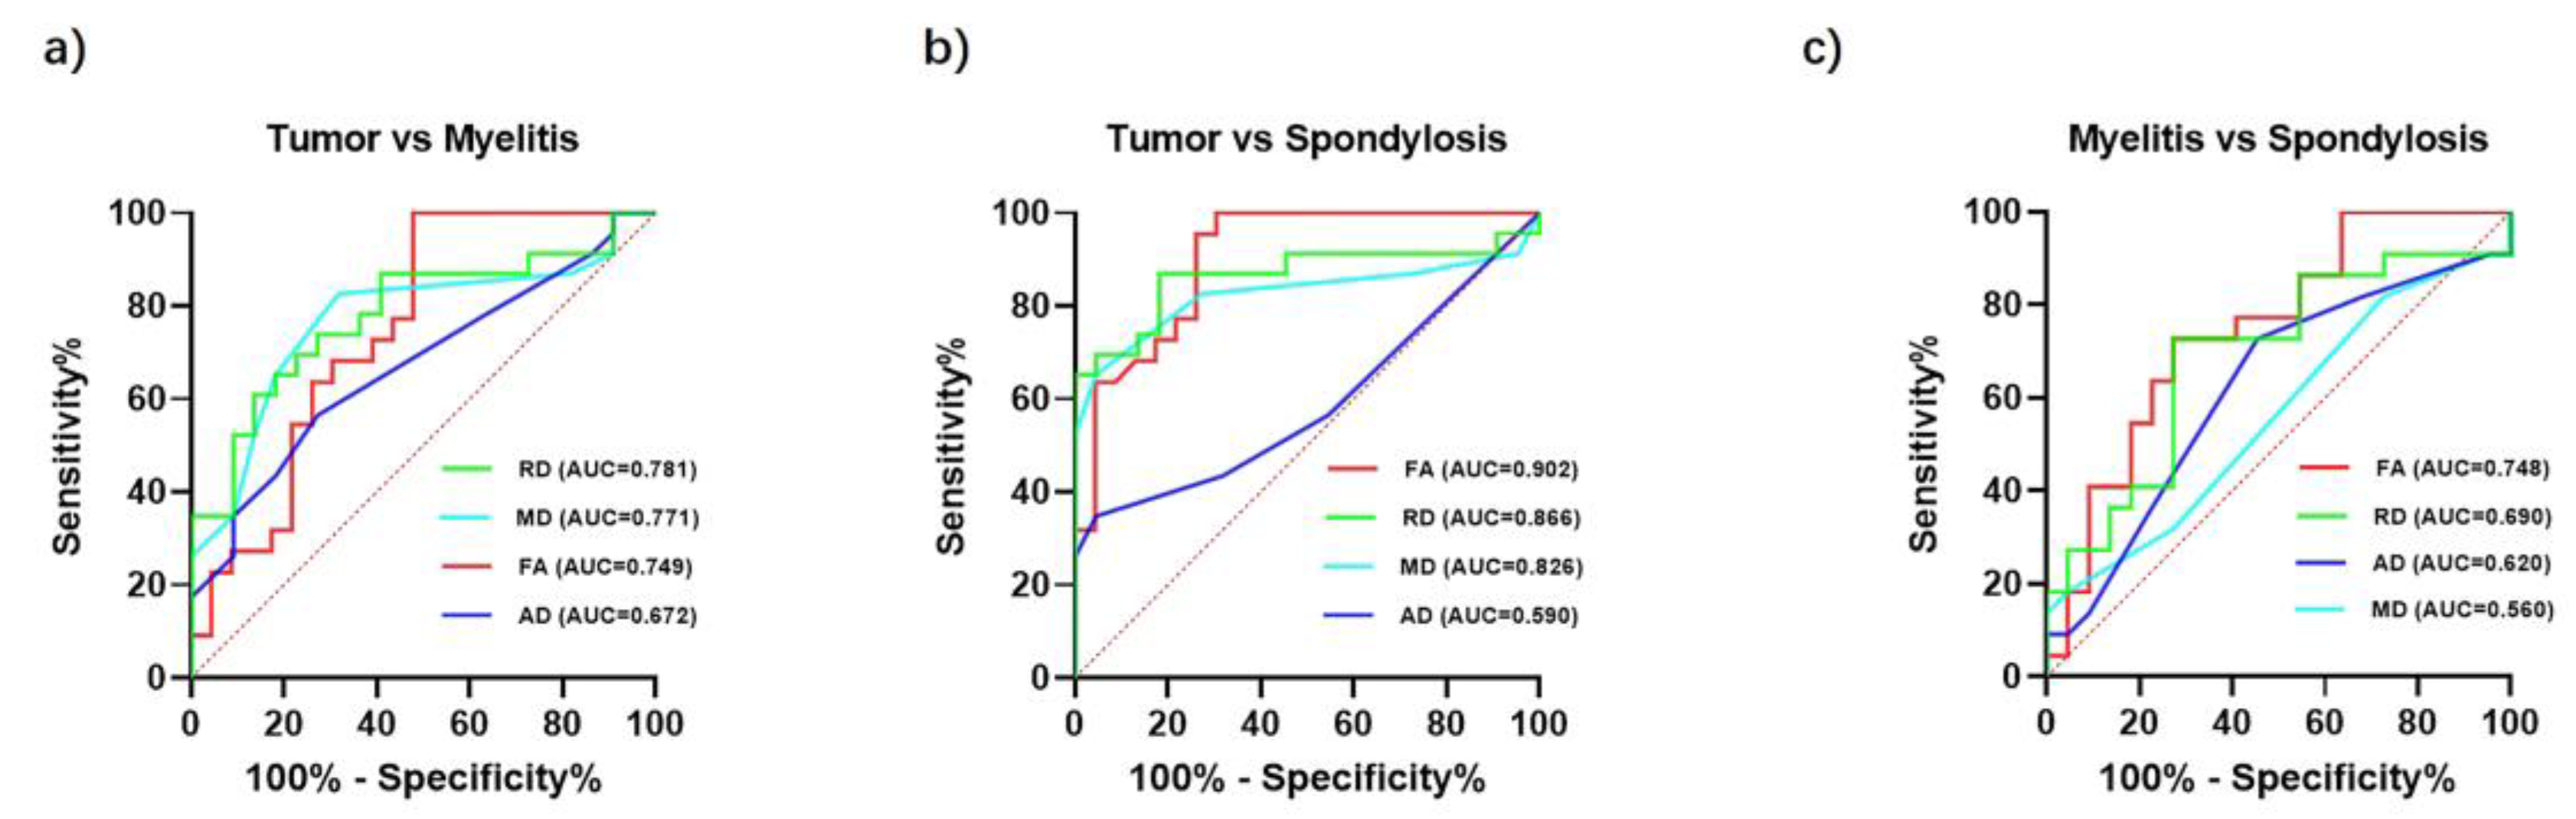

3.3. Discriminative Power of DTI Indicators in Spinal Pathologies

3.4. FA Correlations with Disease Severity in Myelitis and Spinal Tumors